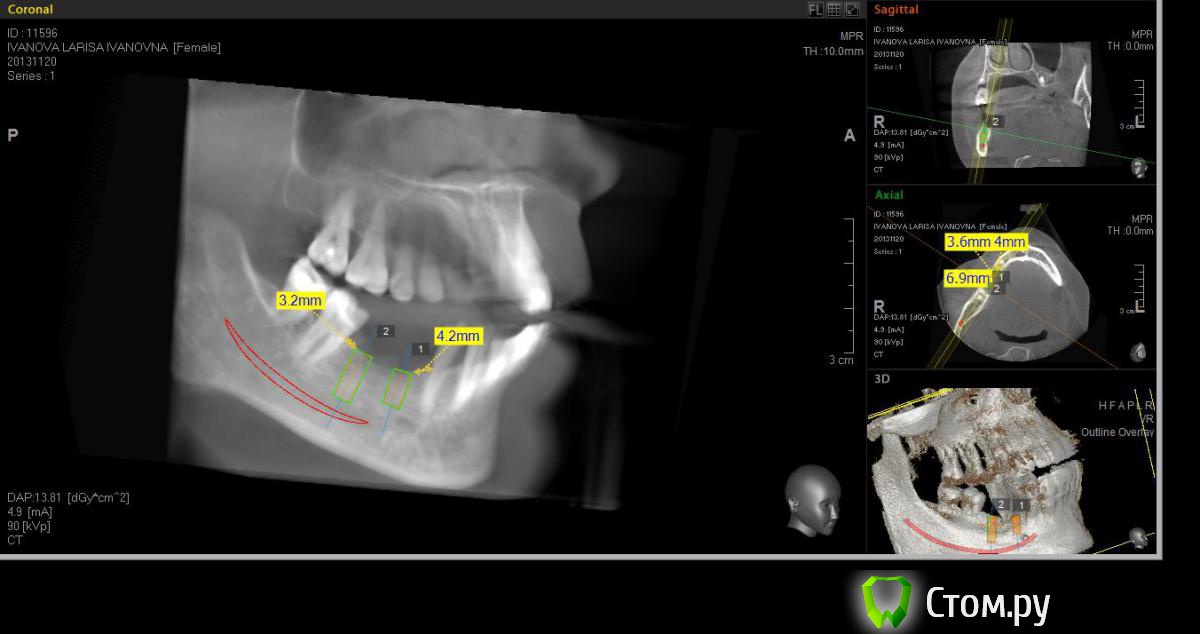

Neilrus Опубликовано 2 марта, 2014 Поделиться Опубликовано 2 марта, 2014 (изменено) Здравствуйте, коллеги, уделите 6 минут новичку…у меня тут проблема, она абсолютно не проблема для того, кто хоть пару раз делал расщепление гребня,а я вот только курсы закончил и у меня планируется через 7 дней операция. Вроде все понял, но пока стремаюсь.Посморите снимки, пожалуйста, а я напишу тот протокол, который хочу применить, как на курсах понял, поправьте, если что не так )) Спросил бы у лектора, но ведь так всегда, да?)Планирую иплантаты по месту 45,46 зубов.Гребень узкий в обл 45 з и близко нч нерв, как раз поднимается к ментальному отвертстию. С этим и связан страх. Никаких транспозиций делать пока не готов. В арсенале нет пьезотома пока, вот пару таких операций сделаю и куплю.Планирую поставить 4,2*8 для 45 зуба и 4,2*11,5 для 46 зуба (Мis Seven) . Соединю коронки, т.к. премоляр коротковат. Итак, план по захвату таков:1)Разрез чуть язычнее середины гребня, откидываем слиз-надк лоскут с аккуратностью в области менталиса.2)По центру гребня делаем горизонтальный распил сепарационным диском диаметром 7 не доходя до зубов по 3 мм. Глубина распила получается 3,3. Потом беру диск 10 и глубина уже 4,8.3)Мелким 7мм диском делаю дистально вертикальный распил на глубину 3,3 длиной с длину имплантата моляра 11,5, а медиально тем же диском на длину 4-5 мм, ниже страшно, боюсь нерв задеть. На верхушке гребня соединяем распилы (черные линии на моем рисунке). Делаем бором твердосплавным шаром компактостеотомию в преполагаемом месте перелома.4)Берем долото и вставляем в горизонтальный разрез и постукиваниями молоточка продвигаем его на глубину до 8мм по всей длине разреза (длина миниального импланта). Чуть покачивая из стороны в сторону, при этом убирая закругления от диска внутри горизонтального распила. (На рисунке, который сам нарисовал – это красная зона).5)Немного раздвинув края в месте предполагаемых имплантатов пилотом 2мм прохожу на глубину имплантатов. Проверяем параллельность.6)Загоняю по очереди мисовские компрессионные винты на глубину имплантатов до диаметра третьего винта 2,4- 3,7 (т.к. импланты 4,2)7)Теперь они вроде как должны быть нормально раздвинуты ( здесь я не понял, нужно проходить фрезами из хир набора или так хорошо войдут) Может финишной фрезой пройти хотя бы на всю глубину имплантатов? Подскажите, пожалуйста.8)Дальше заполняю пустоты MP3, фиксирую пинами MCT 2.75 мембрану evolution толстую на 2 мм ниже коспактостеотомии, перекидываю на язычную сторону под надкостницу краешек запихиваю.9)Мобилизую лоскут, ушиваю все наглухо и надеюсь на лучшее. ВОПРОСЫ:1)не коротковат ли имплант 4,2*8, но ведь я соединю их? Можно немного наклонить его медиально, выход шахты оставить там же, но апикальную часть ближе к моляру, тогда длина 10 выйдет, но там и так не получается соостно с зубами имплант размстить, а тут его и такая ангуляция, не хорошо, я думаю.2)Отслойка лоскута медиально- правильно я написал или порвется тогда и лучше рассечь связку на 44 и медиально вниз.3)Фрезы хирургические нужно использовать при нормальном раздвигании краев гребня? Кстати, нормально-это сколько для диаметра имплантата 4,24)Язычно нужно как-то дополнительно фиксировать мембрану?5)MP3 мешать с аутокостью и кровью из ловушки?6)Как лоскут мобилизовать медиально рядом с ментальным нервом? Пластика зкпд будет одновременно с открытием.Спасибо вам за ваше время ) Изменено 8 мая, 2014 пользователем Bier Ссылка на комментарий